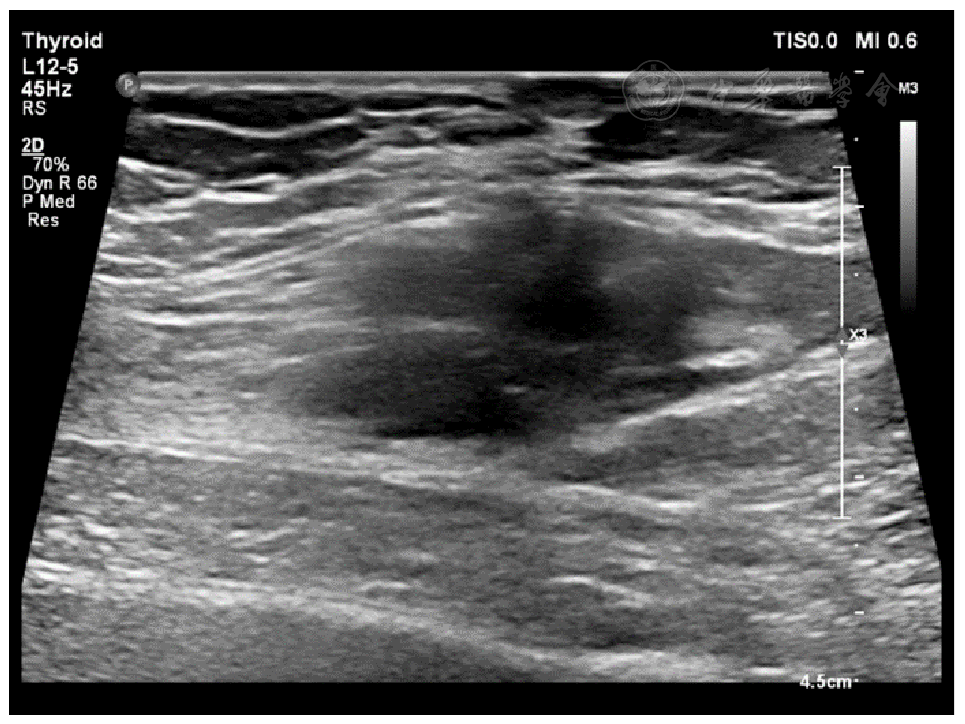

图1 腹壁型侵袭性纤维瘤病长轴的二维灰阶超声图像注:病灶长轴与肌纤维走向一致,浸润方向沿肌层水平方向,垂直于肌层方向的病灶边界清晰(探头频率5~12 MHz)。

10例腹壁侵袭性纤维瘤病患者年龄29~64岁,中位年龄34.5岁;女性患者9例,男性患者1例。10例患者均为单发病灶,且均发生于腹壁肌层。超声表现:低回声为主(10/10例,100%),沿肌层平行生长(10/10例,100%),沿肌层水平方向浸润性生长(7/10例,70%),在垂直于肌层的方向上病灶边界清晰(10/10例,100%),内部回声不均匀(9/10例,90%),内部未见钙化及液性暗区(10/10例,100%)。

The ages of the 10 patients with aggressive fibromatosis of the abdominal wall ranged from 29 to 64 years (median age 34.5 years), including 9 female patients and 1 male patient. All 10 patients had single lesions and all occurred in the muscular layer of the abdominal wall. The ultrasound manifestations were mainly hypoechoic (10/10 cases, 100%), parallel growth along the muscular layer (10/10 cases, 100%), infiltrative growth along the horizontal direction of the muscular layer (7/10 cases, 70%), clear lesion boundaries in the direction perpendicular to the muscular layer (10/10 cases, 100%), and uneven internal echoes (9/10 cases, 90%). No calcification or liquid dark areas were observed internally (10/10 cases, 100%).